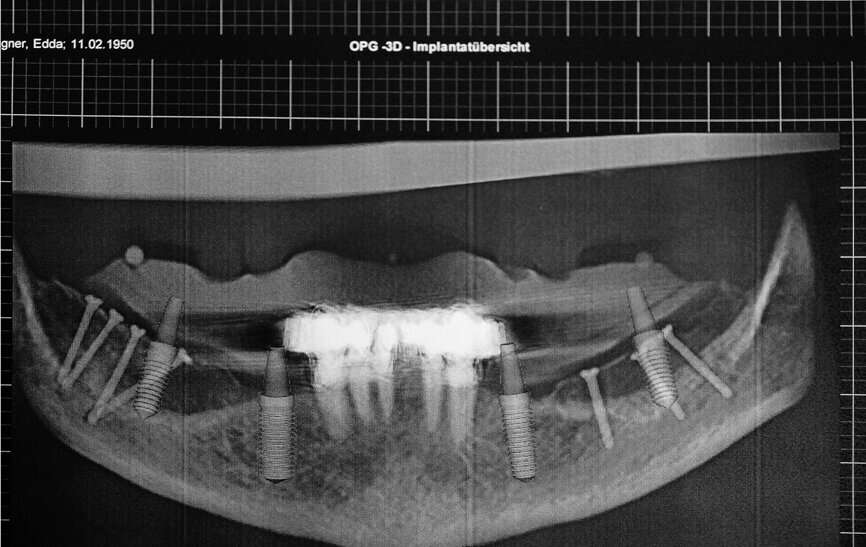

Figs. 12a et b : Tomographie panoramique dentaire virtuelle montrant les positions des implants numériquement définies en 3D dans le maxillaire (a) et la mandibule (b).

La radiographie panoramique dentaire a révélé une perte osseuse d’environ dix pour cent dans la dimension verticale et de quinze pour cent dans la dimension horizontale dans le maxillaire et la mandibule. Après le diagnostic définitif et la planification, nous avons examiné les options de restauration possibles et les autres solutions. La mâchoire ayant été exposée aux rayons, une prothèse totalement a appui muqueux n’était pas indiquée, et la présence de la xérostomie ne garantissait pas une maintenance convenable d’une telle prothèse. Par conséquent, la seule solution médicale raisonnable et pratique était la pose d’implants dentaires, six dans le maxillaire et six dans la mandibule, suivie de la mise en place d’une prothèse fixe implanto-portée.

Le patient a été préparé pour le traitement implantaire guide par ordinateur. Une imagerie CBCT du patient portant le guide radiologique a été réalisée et les images DICOM acquises ont été traitées à l’aide du logiciel CTV. La planification effectuée avec ce logiciel a produit un rapport dans lequel les coordonnées de chacun des trois points médians des billes étaient définies et le prothésiste a donc pu orienter et reproduire le guide chirurgical (Figs. 12a et b). Les gabarits de forage ont été élaborés sur une réplique du maître-modèle à l’aide d’une technique de thermoformage. Par la suite, les manchons de forage ainsi que leurs douilles ont été incorporés dans le gabarit de forage constitue du modèle en plastique fabrique au moyen du procédé additif. La base transparente du gabarit a permis une évaluation peropératoire de la position de ce gabarit sur le tégument grâce à l’ischémie uniforme causée par la pression de contact pendant l’implantation (Fig. 13).